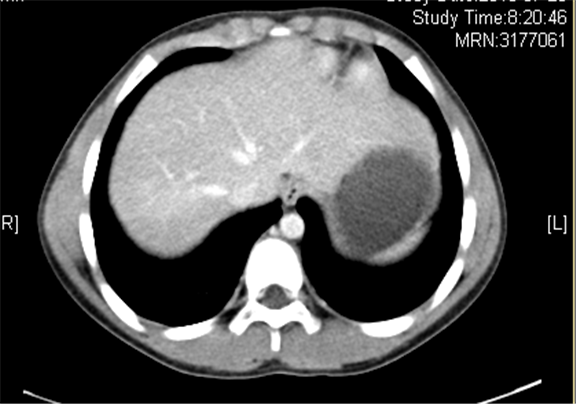

上腹部增强CT示:右侧肾上腺区占位性病变,考虑恶性肿瘤,右侧肾上腺神经母细胞瘤可能性大,请结合临床综合评价。

术前CT检查:

静脉期